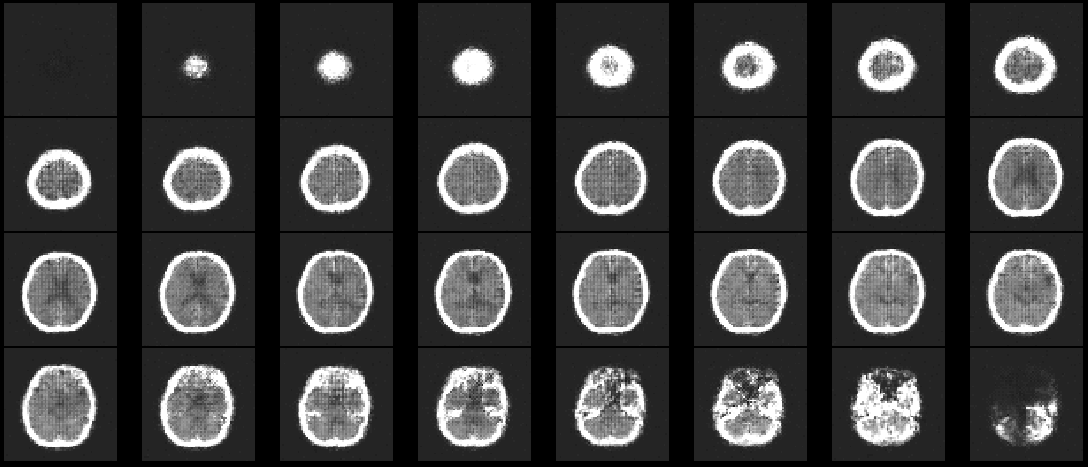

Refer to caption

Figure 15: Fictional image of a BCT generated with the flow-based generative model.

Finally, a fictional image generated for BCTs is shown in Fig. 15.